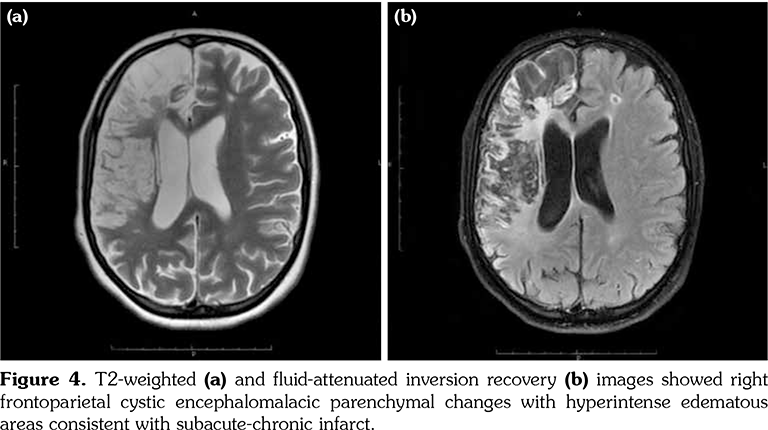

A 14-year-old female patient referred to our clinic with headache and dizziness for two weeks and loss of consciousness for about 10 minutes. On admission, the blood pressure was 90/60 mmHg and all peripheral pulses were palpable. Her body weight was above 97th percentile for her age and body mass index was 33. The fundus examination and other organ systems were essentially normal. Laboratory studies revealed erythrocyte sedimentation rate (ESR) as 108 mm/hour and C-reactive protein (CRP) as 7.5 mg/dL (0-0.8), while other measurements were normal. Urinalysis revealed microscopic hematuria and proteinuria of 31.9 mg/m2/hour in 24-hour urine collection. The cerebrospinal fluid examination showed no abnormalities. Cranial magnetic resonance imaging (MRI) showed multiple millimetric hyperintense deep white matter lesions on T2-weighted imaging (Figure 1). Intracranial and extracranial arteries were normal in magnetic resonance angiography (MRA). Renal biopsy findings were interpreted as FSGS (Figure 2). Patient was considered as cerebral vasculitis and incidental FSGS. Pulse methylprednisolone therapy for three consecutive days was initiated and continued with oral prednisolone. At four years of follow-up, proteinuria decreased to 5-15 mg/m2/hour, and ESR and CRP were normal. Repeated brain MRI and MRA examinations showed no new lesions. Four years later, at the age of 18, on a routine examination, both radial artery pulses were absent and the blood pressure could not be measured. Significant bruit was heard on the left carotid artery. Laboratory studies revealed ESR as 43 mm/hour and CRP as 2.46 mg/dL. Aortic MRA revealed diffuse wall thickening and contrast enhancement in the arcus aorta and its many main branches (Figure 3). Takayasu arteritis diagnosis was established according to the European League Against Rheumatism/ Paediatric Rheumatology International Trials Organisation/Paediatric Rheumatology European Society criteria.[2] Methotrexate was begun, and daily prednisolone was continued. Four months after the diagnosis of TA, left-sided hemiparesis developed. Brain MRI demonstrated a wide cerebral infarct at the right anterior vascular territory (Figure 4). Brain and neck computed tomography angiography showed total occlusion of the right internal carotid artery. Vascular involvement of the right common carotid artery was progressed to preocclusive stenosis. Diameters of the right anterior and middle cerebral arteries were thin and fed by the posterior and anterior communicating arteries (Figure 5). Tocilizumab treatment was started at 8 mg/kg every four weeks. At follow- up with 2.5 years of tocilizumab treatment, the patient's clinical condition improved slightly, and no new symptoms developed. A written informed consent was obtained from the patient.